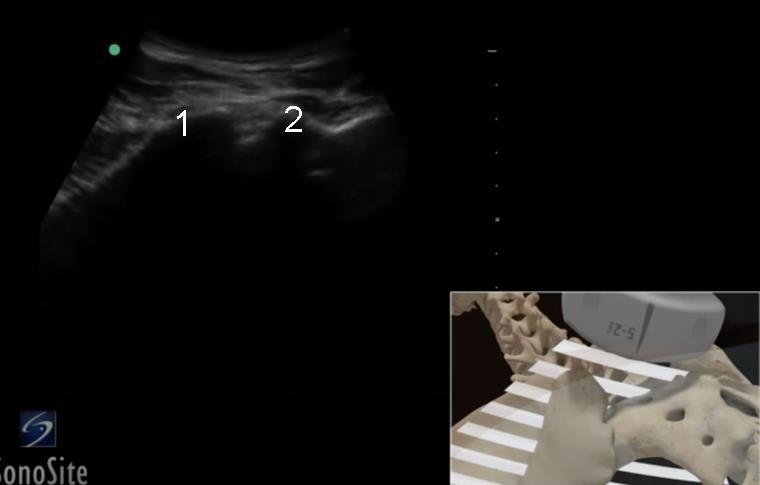

Cadera - Ilion y sacro - Imagen

Ilion

Sacro